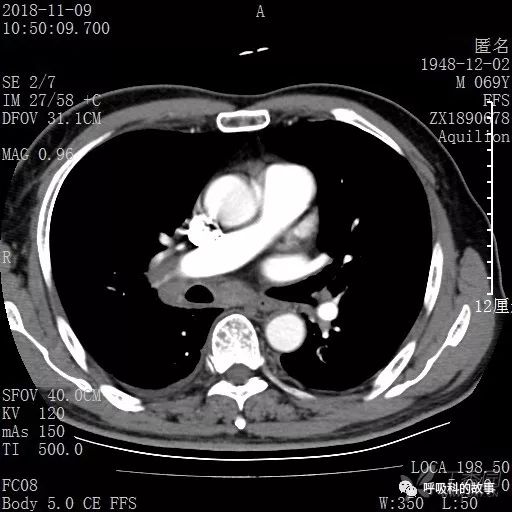

胸部增强CT示右肺门占位伴远端阻塞性肺炎,纵膈、右肺门、右侧颈根部、右侧腋下及肝门部肿大淋巴结。两侧胸腔少量积液。

肺窗CT